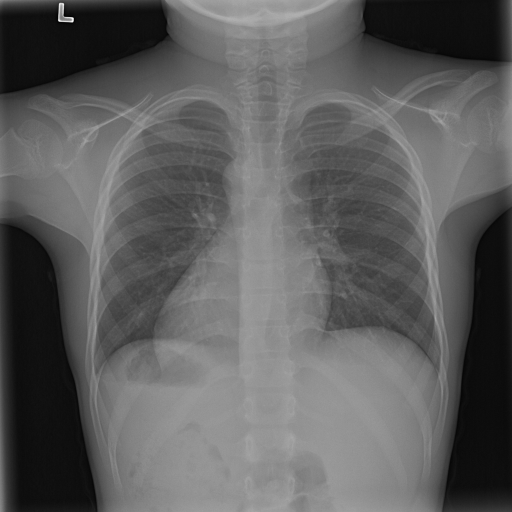

(a) Original

case 1

(b) ϵ=103HWitalic-ϵsuperscript103𝐻𝑊\epsilon=10^{3}\cdot H\cdot W

(c) ϵ=102HWitalic-ϵsuperscript102𝐻𝑊\epsilon=10^{2}\cdot H\cdot W

(d) ϵ=101HWitalic-ϵsuperscript101𝐻𝑊\epsilon=10^{1}\cdot H\cdot W

(e) Original

case 2

(f) ϵ=103HWitalic-ϵsuperscript103𝐻𝑊\epsilon=10^{3}\cdot H\cdot W

(g) ϵ=102HWitalic-ϵsuperscript102𝐻𝑊\epsilon=10^{2}\cdot H\cdot W

(h) ϵ=101HWitalic-ϵsuperscript101𝐻𝑊\epsilon=10^{1}\cdot H\cdot W

(i) Original

case 3

(j) ϵ=103HWitalic-ϵsuperscript103𝐻𝑊\epsilon=10^{3}\cdot H\cdot W

(k) ϵ=102HWitalic-ϵsuperscript102𝐻𝑊\epsilon=10^{2}\cdot H\cdot W

(l) ϵ=101HWitalic-ϵsuperscript101𝐻𝑊\epsilon=10^{1}\cdot H\cdot W

(m) Original

case 4

(n) ϵ=103HWitalic-ϵsuperscript103𝐻𝑊\epsilon=10^{3}\cdot H\cdot W

(o) ϵ=102HWitalic-ϵsuperscript102𝐻𝑊\epsilon=10^{2}\cdot H\cdot W

(p) ϵ=101HWitalic-ϵsuperscript101𝐻𝑊\epsilon=10^{1}\cdot H\cdot W

Figure 2: ϵitalic-ϵ\epsilon-LDP-processed CXR images obtained with DP-GLOW.

In Fig. 1, we show four ϵitalic-ϵ\epsilon-LDP-processed CXR images of clinical cases obtained with the image domain LDP, which directly imposes the Laplace mechanism on the input image, with different privacy budgets together with the original images. Fig. 2 shows four ϵitalic-ϵ\epsilon-LDP-processed CXR images of clinical cases obtained with DP-GLOW and different privacy budgets together with the original images. In case 1 for DP-GLOW, there is decreased permeability in the bilateral hilar regions. Although this hilar opacity tends to be preserved with a larger privacy budget, the entire image is degraded when the privacy budget becomes 101HWsuperscript101𝐻𝑊10^{1}\cdot H\cdot W. A similar tendency is observed in the images of all the four cases for DP-GLOW; for example, in case 4 with ϵ=101HWitalic-ϵsuperscript101𝐻𝑊\epsilon=10^{1}\cdot H\cdot W, the lung opacity suggesting pneumonia in the right lower lung field is well preserved, while the entire image is degraded.